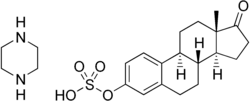

| Formula | C22H32N2O5S |

| Molar mass | 436.57 g·mol−1 |

| 3D model (JSmol) | |